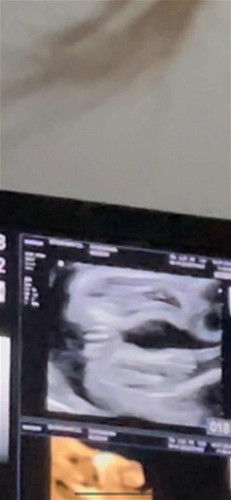

แม่ๆท่านไหนซาวด์ได้ลูกผู้หญิงบ้างคะ? อยากรู้ว่าเป็นแบบนี้ไหม??

คุณหมอบอกผู้หญิง100%แต่แม่แอบกังวลเพราะเห็นแม่บางท่าน ซาวด์ได้ผู้หญิงแต่คลอดออกมาเป็นผู้ชาย ยิ่งคนรู้จักพึ่งคลอดลูกเมื่อเดือนที่แล้วซาวด์ได้ผู้ชายแต่คลอดมาเป็นผู้หญิงแม่ยิ่งกลัวไปใหญ่ ใจอยากได้ผู้หญิงค่ะ

ในรูปเป็นกลีบชัดเลยนะคะ ของเราเป็นผช.ซาวด์ออกมาเห็นเป็นก้อนไข่ค่ะ ไม่มีรอยกลีบแบบนี้ค่ะ

บ้านนี้เหมือนกันค่ะ ป้าหมอบอกกลีบใหญ่ขนาดนี่ไม่ต้องกลัวเป็นผู้ชายนะคุณแม่😂